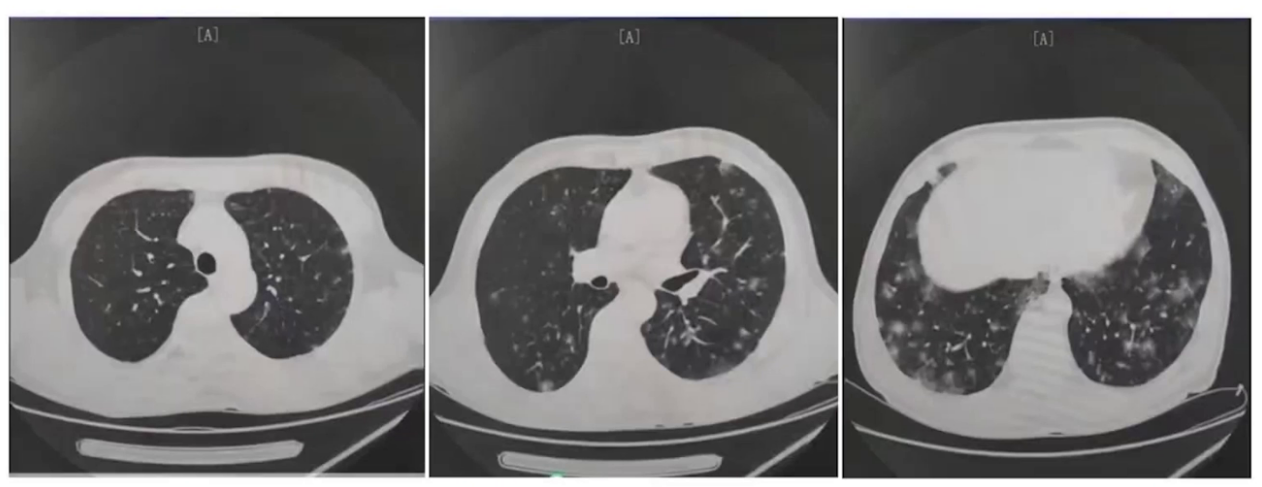

2023年8月30日胸部CT(外院):

2023年9月15日胸部CT(外院):

2023年10月31日胸部CT(外院):